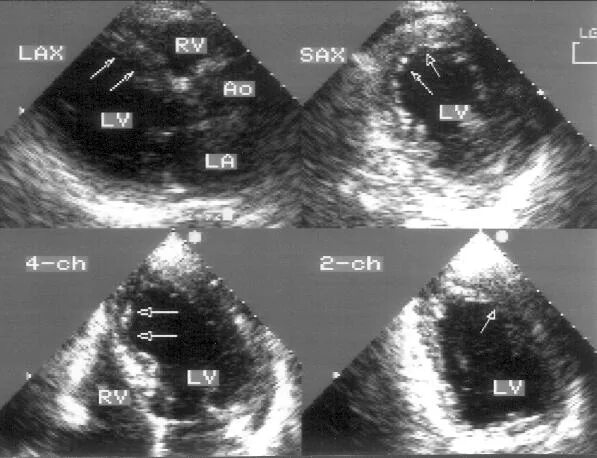

Гипокинез базального сегмента